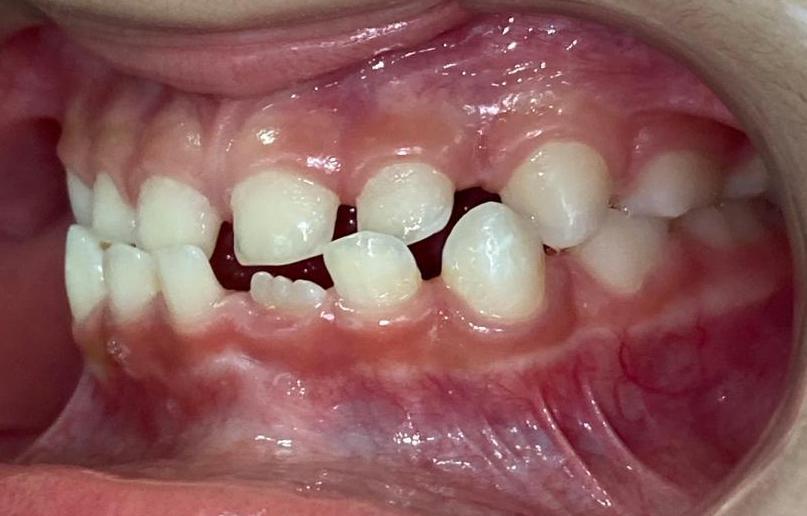

R.P.B.

ORTODONTIA MIOFUNCIONAL